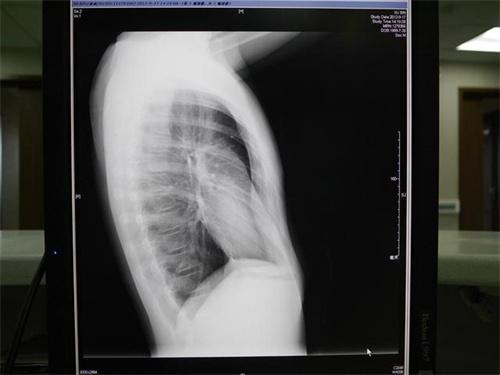

顧海濤教授仔細觀察后發(fā)現(xiàn)小安胸骨下段,以及肋骨都向內(nèi)凹陷呈現(xiàn)漏斗這樣的形狀,這種情況是先天胸廓畸形也是常說的漏斗胸,胸骨下段會向內(nèi)凹陷外觀形似漏斗。孩子比較小的時候,癥狀不明顯時,大多數(shù)家長都容易把漏斗胸當成孩子缺鈣耽誤了治療。